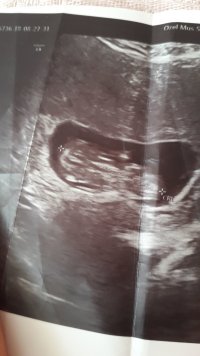

Merhaba ,

Nub teorisiyle cinsiyeti uzman hekimler belirleyebiliyormuş. Bu yüzden doğruluk payı var.

Nub teorisi ile ilgili istatistiki bilgiler şöyledir;

1 hafta sonunda, doğruluk oranı 48 yüzde olduğu

12 hafta sonunda, doğruluk oranı 91 yüzde olduğu

13 hafta sonunda, doğruluk oranı 94 yüzde olduğu